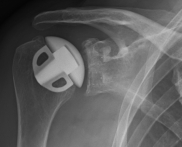

Abbildung3Abbildung4Surface replacement ("cap prosthesis" of the humeral head) in cases of mild omarthrosis and still well-preserved glenoid cavity

links: X-ray image of a cap prosthesis ("surface replacement")

right: cap prosthesis ("surface replacement", type "Durom" Fa. Zimmer)gkl